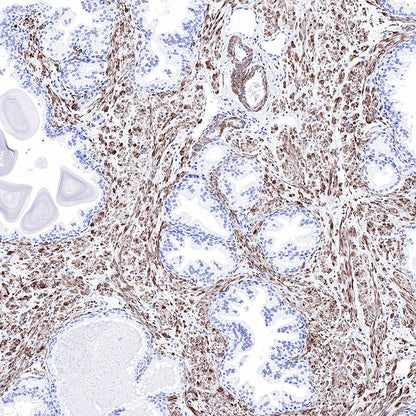

IHC shows positive staining in paraffin-embedded human prostatic hyperplasia. Anti-Smooth Muscle Myosin Heavy Chain (SMMHC) antibody was used at 1/1000 dilution, followed by a HRP Polymer for Mouse & Rabbit IgG (ready to use). Counterstained with hematoxylin. Heat mediated antigen retrieval with Tris/EDTA buffer pH9.0 was performed before commencing with IHC staining protocol.